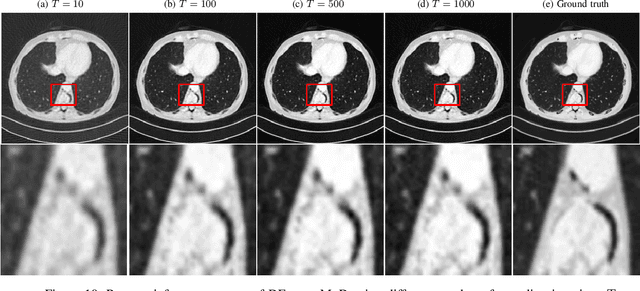

Abstract:Dual-energy X-ray Computed Tomography (DECT) constitutes an advanced technology which enables automatic decomposition of materials in clinical images without manual segmentation using the dependency of the X-ray linear attenuation with energy. However, most methods perform material decomposition in the image domain as a post-processing step after reconstruction but this procedure does not account for the beam-hardening effect and it results in sub-optimal results. In this work, we propose a deep learning procedure called Dual-Energy Decomposition Model-based Diffusion (DEcomp-MoD) for quantitative material decomposition which directly converts the DECT projection data into material images. The algorithm is based on incorporating the knowledge of the spectral DECT model into the deep learning training loss and combining a score-based denoising diffusion learned prior in the material image domain. Importantly the inference optimization loss takes as inputs directly the sinogram and converts to material images through a model-based conditional diffusion model which guarantees consistency of the results. We evaluate the performance with both quantitative and qualitative estimation of the proposed DEcomp-MoD method on synthetic DECT sinograms from the low-dose AAPM dataset. Finally, we show that DEcomp-MoD outperform state-of-the-art unsupervised score-based model and supervised deep learning networks, with the potential to be deployed for clinical diagnosis.